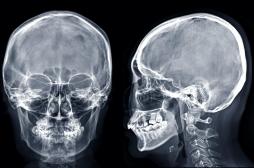

J ai Mal Bras et mains Bras et mains Tête et cou Torse et haut du dos Jambes et pied